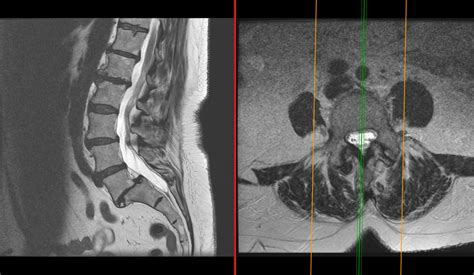

• Imaging tests: Diagnostic imaging tests such as X-rays, MRI, or CT scans may be used to visualize the spine and identify the protrusion.